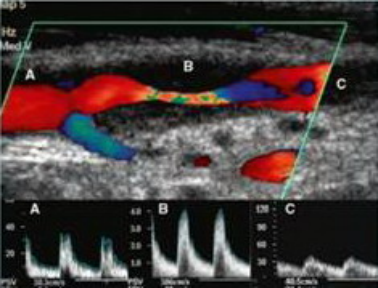

动脉粥样硬化狭窄及其血流动力学改变

2. 心脏及周围血管超声检查:心脏、胸主动脉、颈动脉、椎动脉,腹部大血管、四肢大血管等。